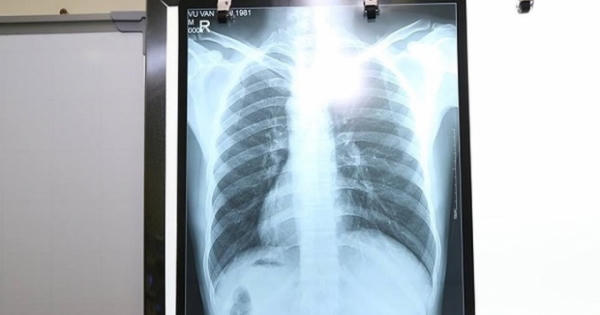

Vào viện vì viêm ruột thừa cấp, anh Vũ Văn H. (Gia Lâm, Hà Nội) được bác sĩ phát hiện bị có phủ tạng đảo ngược hoàn toàn so với bình thường…